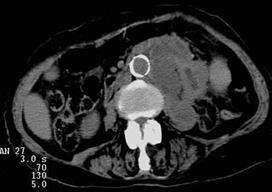

Рис. 6.18. Компьютерная томограмма брюшной полости на уровне L2. Левая почка деформирована с наличием псевдокистозных образований. Правая почка в норме. Абсцесс левой почки.

Рис. 6.19. Компьютерная томограмма брюшной полости на уровне L3. То же наблюдение, что и на предыдущей компьютерной томограмме. Определяется распространение абсцесса левой почки книзу в парааортальной области слева в виде объемного образования неоднородной плотности.